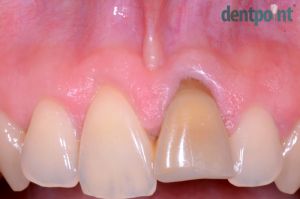

Fémmentes korona és ínyrecesszió fedés

Hölgy páciensünk metszőfogát fémmentes koronával tettük esztétikusabbá illetve visszahúzódott fogínyét ínyrecesszió fedéssel korrigáltuk.

1) Kiindulási helyzet

2) Elszíneződött metszőfog

3) Ínyrecesszió fedése

4) Koronacsere